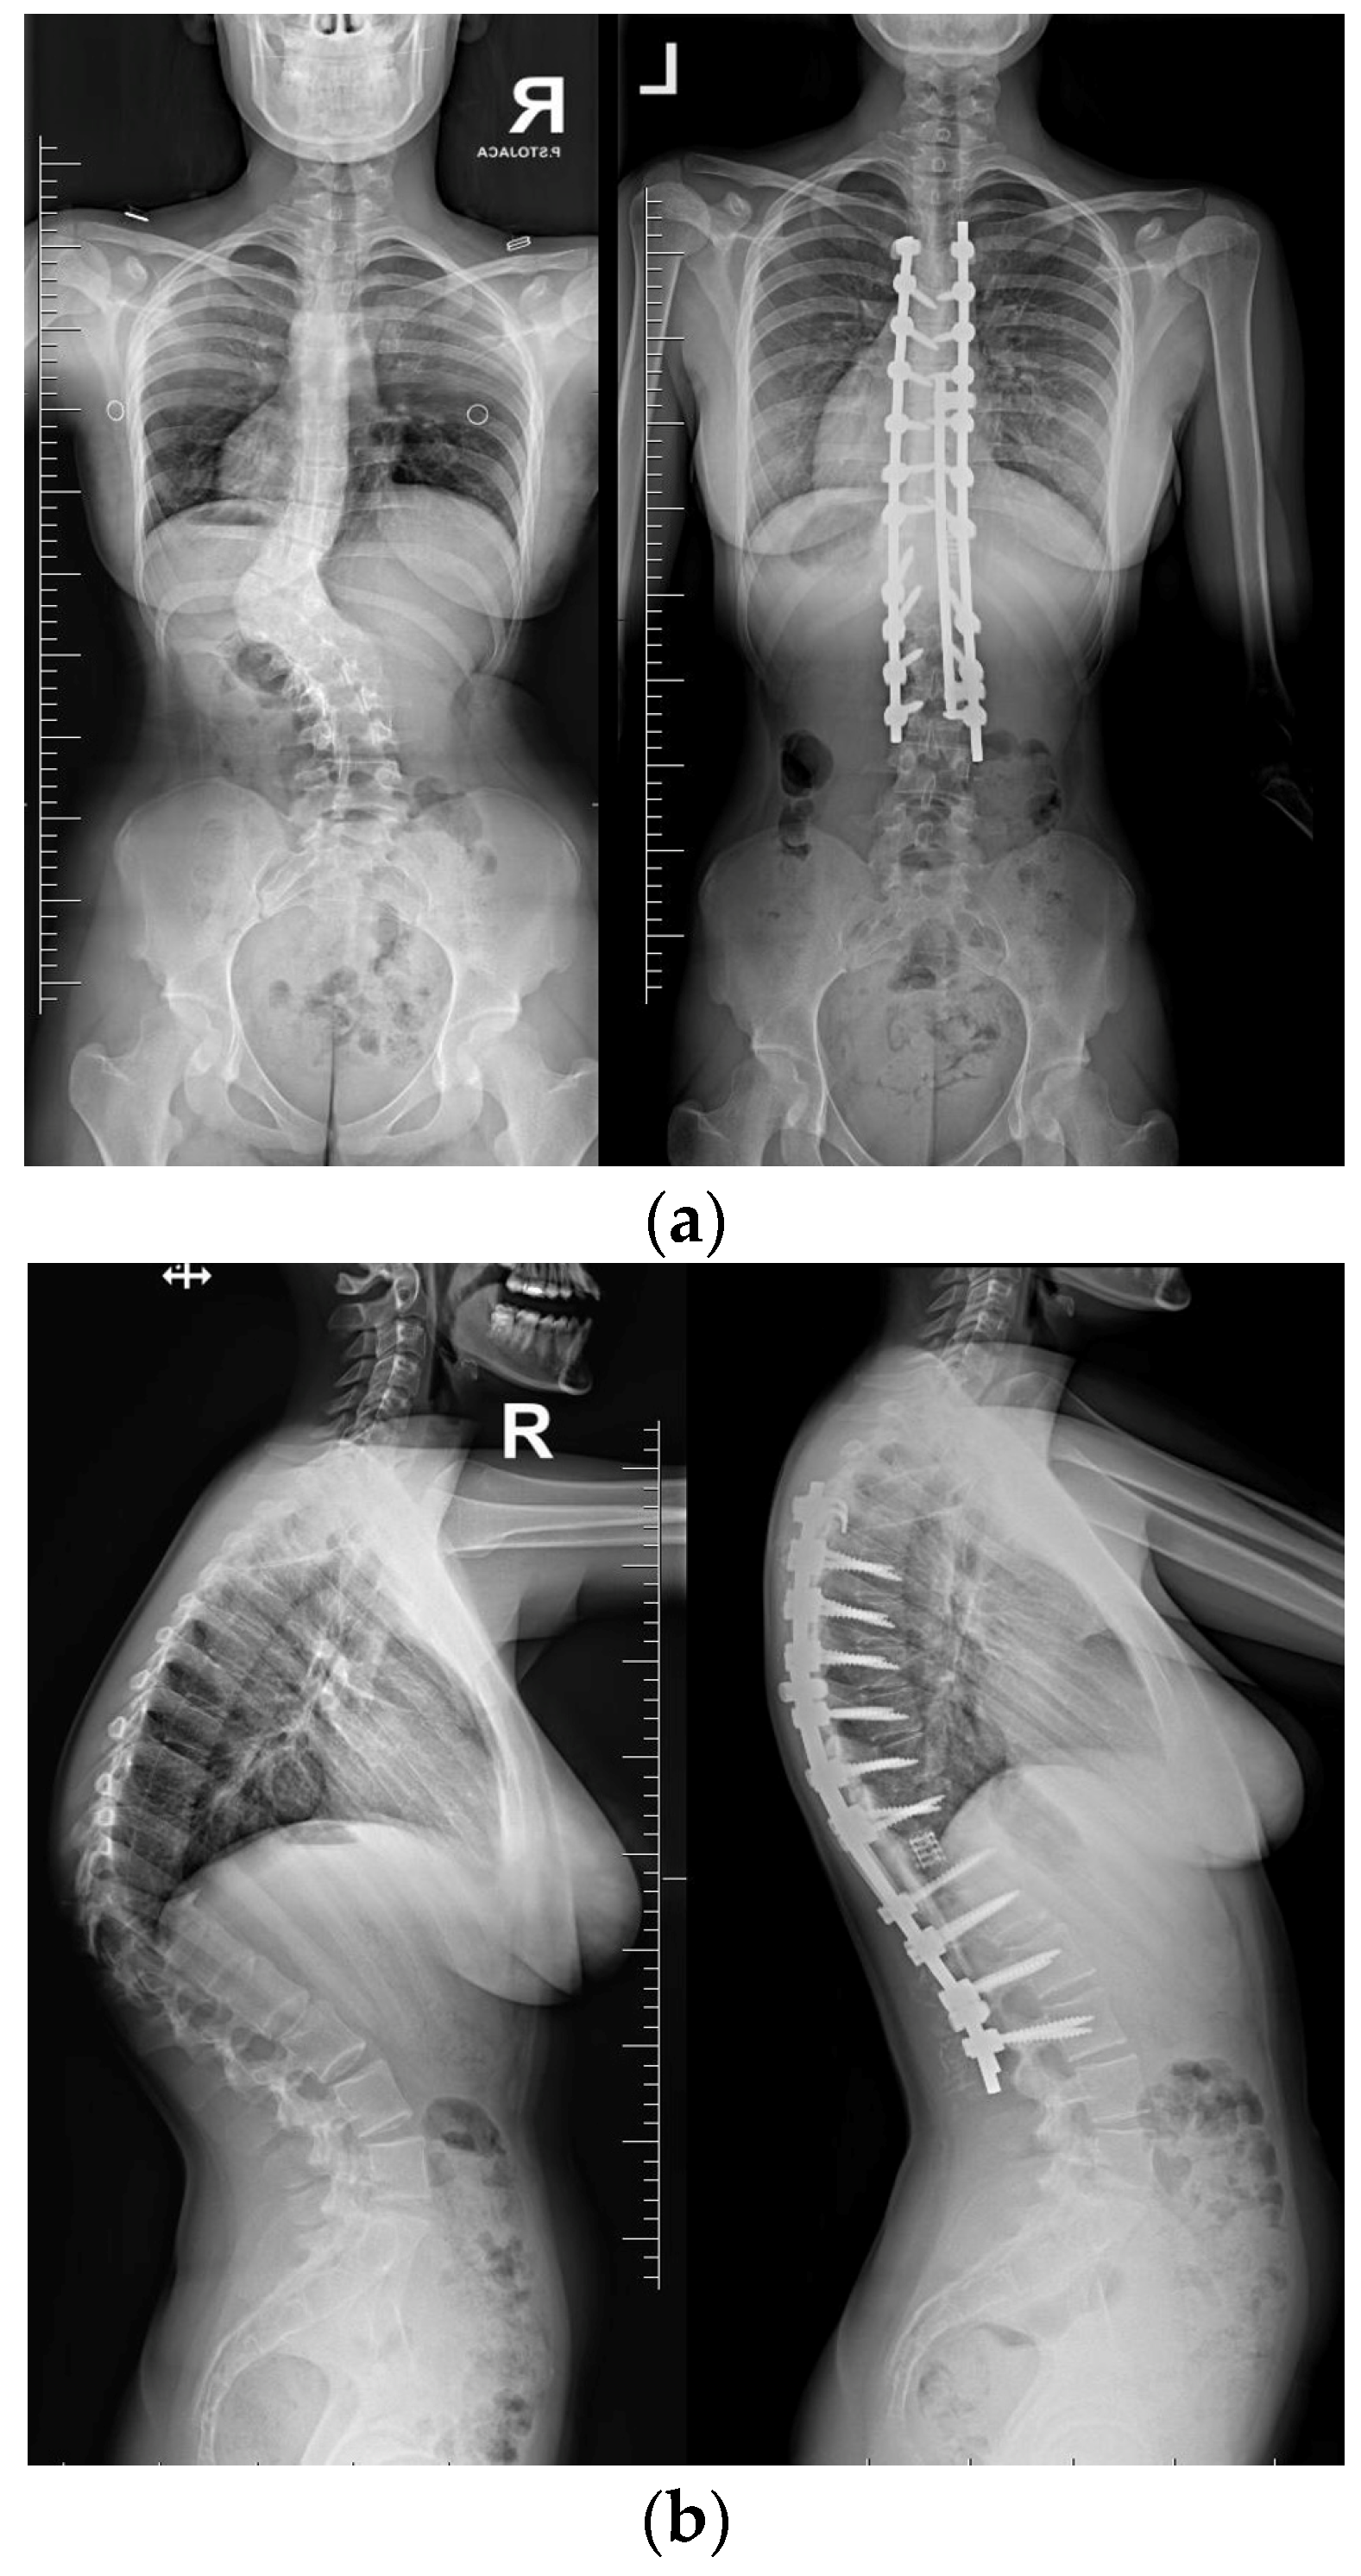

Upon conducting a postoperative physical examination, it was observed that the patient’s shoulder symmetry and rib hump had improved significantly without any neurological or other complications. Figure 9 shows a significant improvement in the patient’s posture, sagittal balance (focal thoracic kyphosis from 108° to 43°), and coronal balance (from 63° to 25°). The patient was discharged 5 days after surgery; no brace was ordered. Figure 10 and Figure 11 show the X-rays and 3D-CT of the patient at the final follow-up.

Figure 10. Standard standing AP (a) and lateral (b) X-rays of the 16-year-old female after undergoing surgical treatment at 2 years of follow-up.